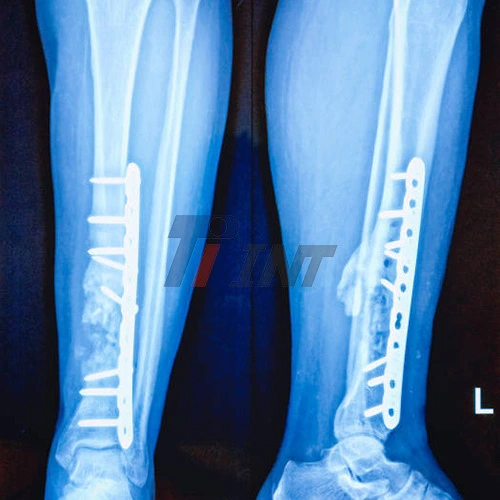

Another advantage of titanium plates is their radiolucency, which means they are partially transparent to X-rays. This property allows for clearer post-operative imaging, enabling surgeons to more easily monitor the healing progress and detect any potential complications. The compatibility of titanium with various imaging modalities, including CT scans and MRI, further enhances its utility in long-term patient follow-up and management.

Regular follow-up appointments with the orthopedic surgeon are essential to monitor the healing progress and ensure proper bone alignment. X-rays or other imaging studies may be performed periodically to assess bone union and implant position. In numerous cases, titanium plates can be cleared out and put inconclusively without causing any issues. In any case, in a few occasions, especially in more youthful patients or those encountering distress, the plates may be evacuated once total bone mending has happened. This choice is made on a case-by-case basis, considering variables such as the patient's age, general well-being, and the particular area of the embed.